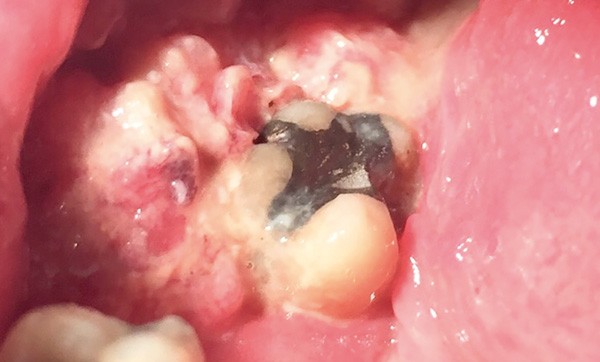

On note un trismus non serré et un œdème jugal droit ; l’examen endo-buccal révèle une lésion dans le vestibule latéro-molaire inférieur droit, ulcéro-bourgeonnante douloureuse, indurée à la palpation, avec un aspect inflammatoire et une légère suppuration (fig. 1). La lésion est adhérente au plan osseux. Une adénopathie sous-mandibulaire droite supra-centimétrique indolore et dure est palpée. Le patient a du mal à s’alimenter.